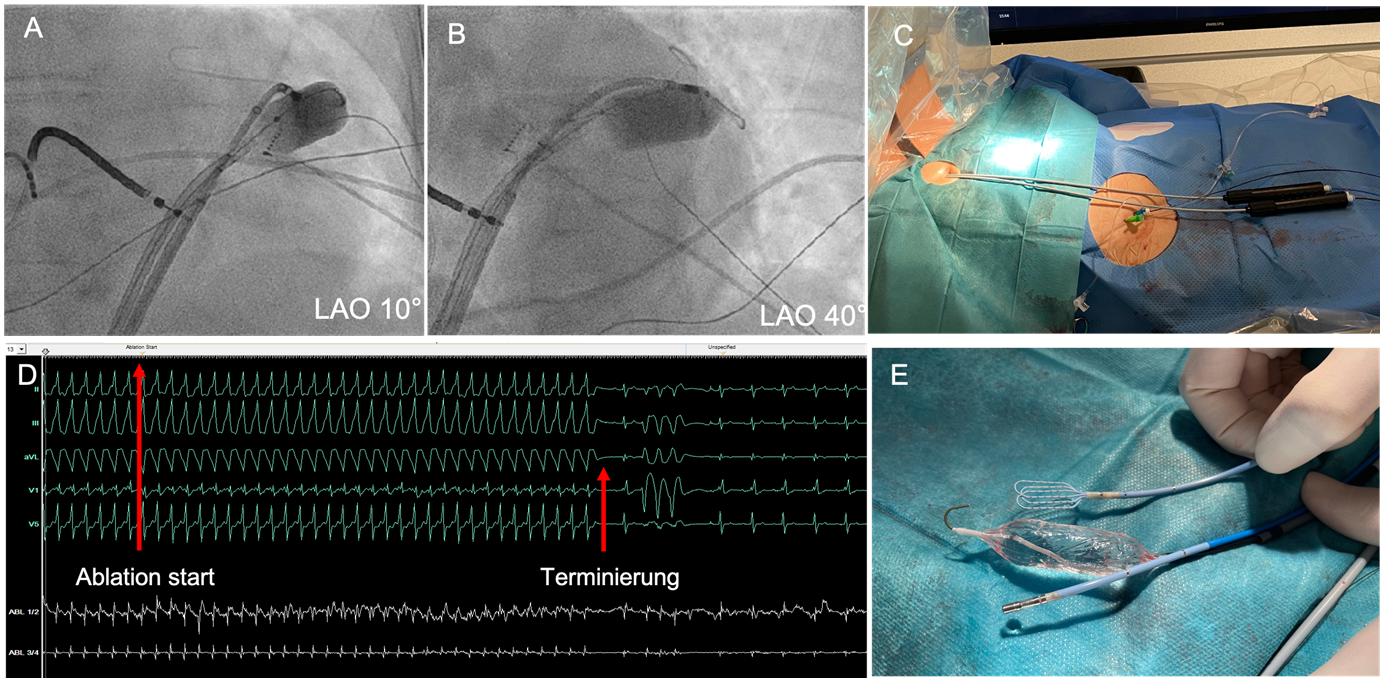

Fluoroskopie von Katheter- und Ballon-Position

Abbildung 3: Fluoroskopie von Katheter- und Ballon-Position in LAO 10° (A) und LAO 40° (B). C: Zugangswege: Zwei steuerbare epikardiale Schleusen, femoral ein venöser Zugang für den RV-Stimulationskatheter, ein arterieller Zugang für invasive RR-Messung und Koronarangiographie. D: Ablation unter laufender VT mit Anstieg der CL und rascher Terminierung. E: Mapping- und Ablationskatheter sowie 18x40 mm-Ballon zur Anhebung des N. phrenicus.